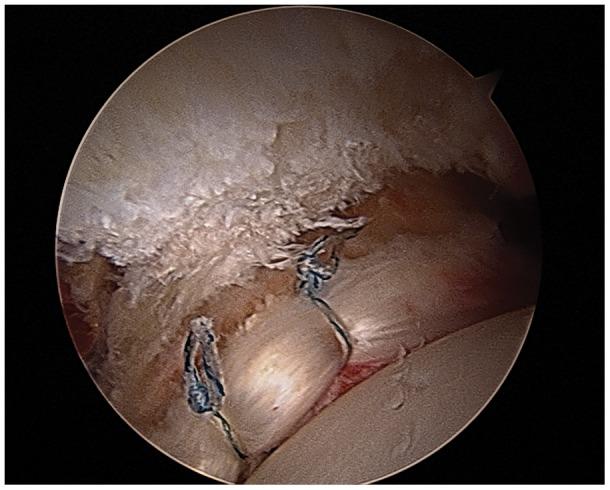

Improvements in hip arthroscopy have allowed FAI to be addressed utilizing the arthroscope. Adequately resecting the underlying osseous abnormalities is essential to improving hip symptomatology and preventing further chondral damage. Additionally, preserving the labrum by repairing the damaged tissue and restoring the suction seal may theoretically help normalize hip mechanics and prevent further arthritic changes. The outcomes of joint-preserving treatment options may be varied in the maturing athlete due to the degree of underlying OA. Irreversible damage to the hip joint may have already occurred in patients with moderate to advanced OA. In the presence of preexisting arthritis, these patients may only experience fair or even poor results after hip arthroscopy, with early conversion to hip replacement. For patients with advanced hip arthritis, total hip arthroplasty remains a treatment option to reliably improve symptoms with good to excellent outcomes and return to low-impact activities.

髋关节镜技术的改进使得可以使用关节镜来解决 FAI 问题。彻底切除潜在的骨性异常对于改善髋关节症状和防止进一步软骨损伤至关重要。此外,通过修复受损组织和恢复抽吸密封来保留盂唇,从理论上讲可以帮助恢复髋关节力学并防止进一步的关节炎变化。由于潜在 OA 的程度不同,关节保留治疗选择的结果在成熟运动员中可能有所不同。在中度至重度 OA 患者中,髋关节可能已经发生了不可逆转的损伤。对于存在先前关节炎的患者,髋关节镜检查后他们可能只会经历一般或甚至较差的结果,早期转为髋关节置换。对于患有晚期髋关节炎的患者,全髋关节置换术仍然是一种可靠的治疗方法,可以改善症状,获得良好至极好的结果,并恢复低影响活动。